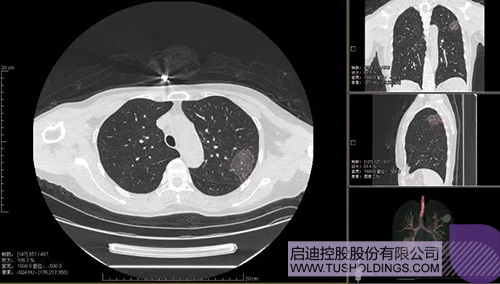

2020年2月11日,九游·官方版在线入口科服投资企业—神州德信推出新冠肺炎检测及量化智能分析系统,积极助力一线医务人员科学精准防疫。